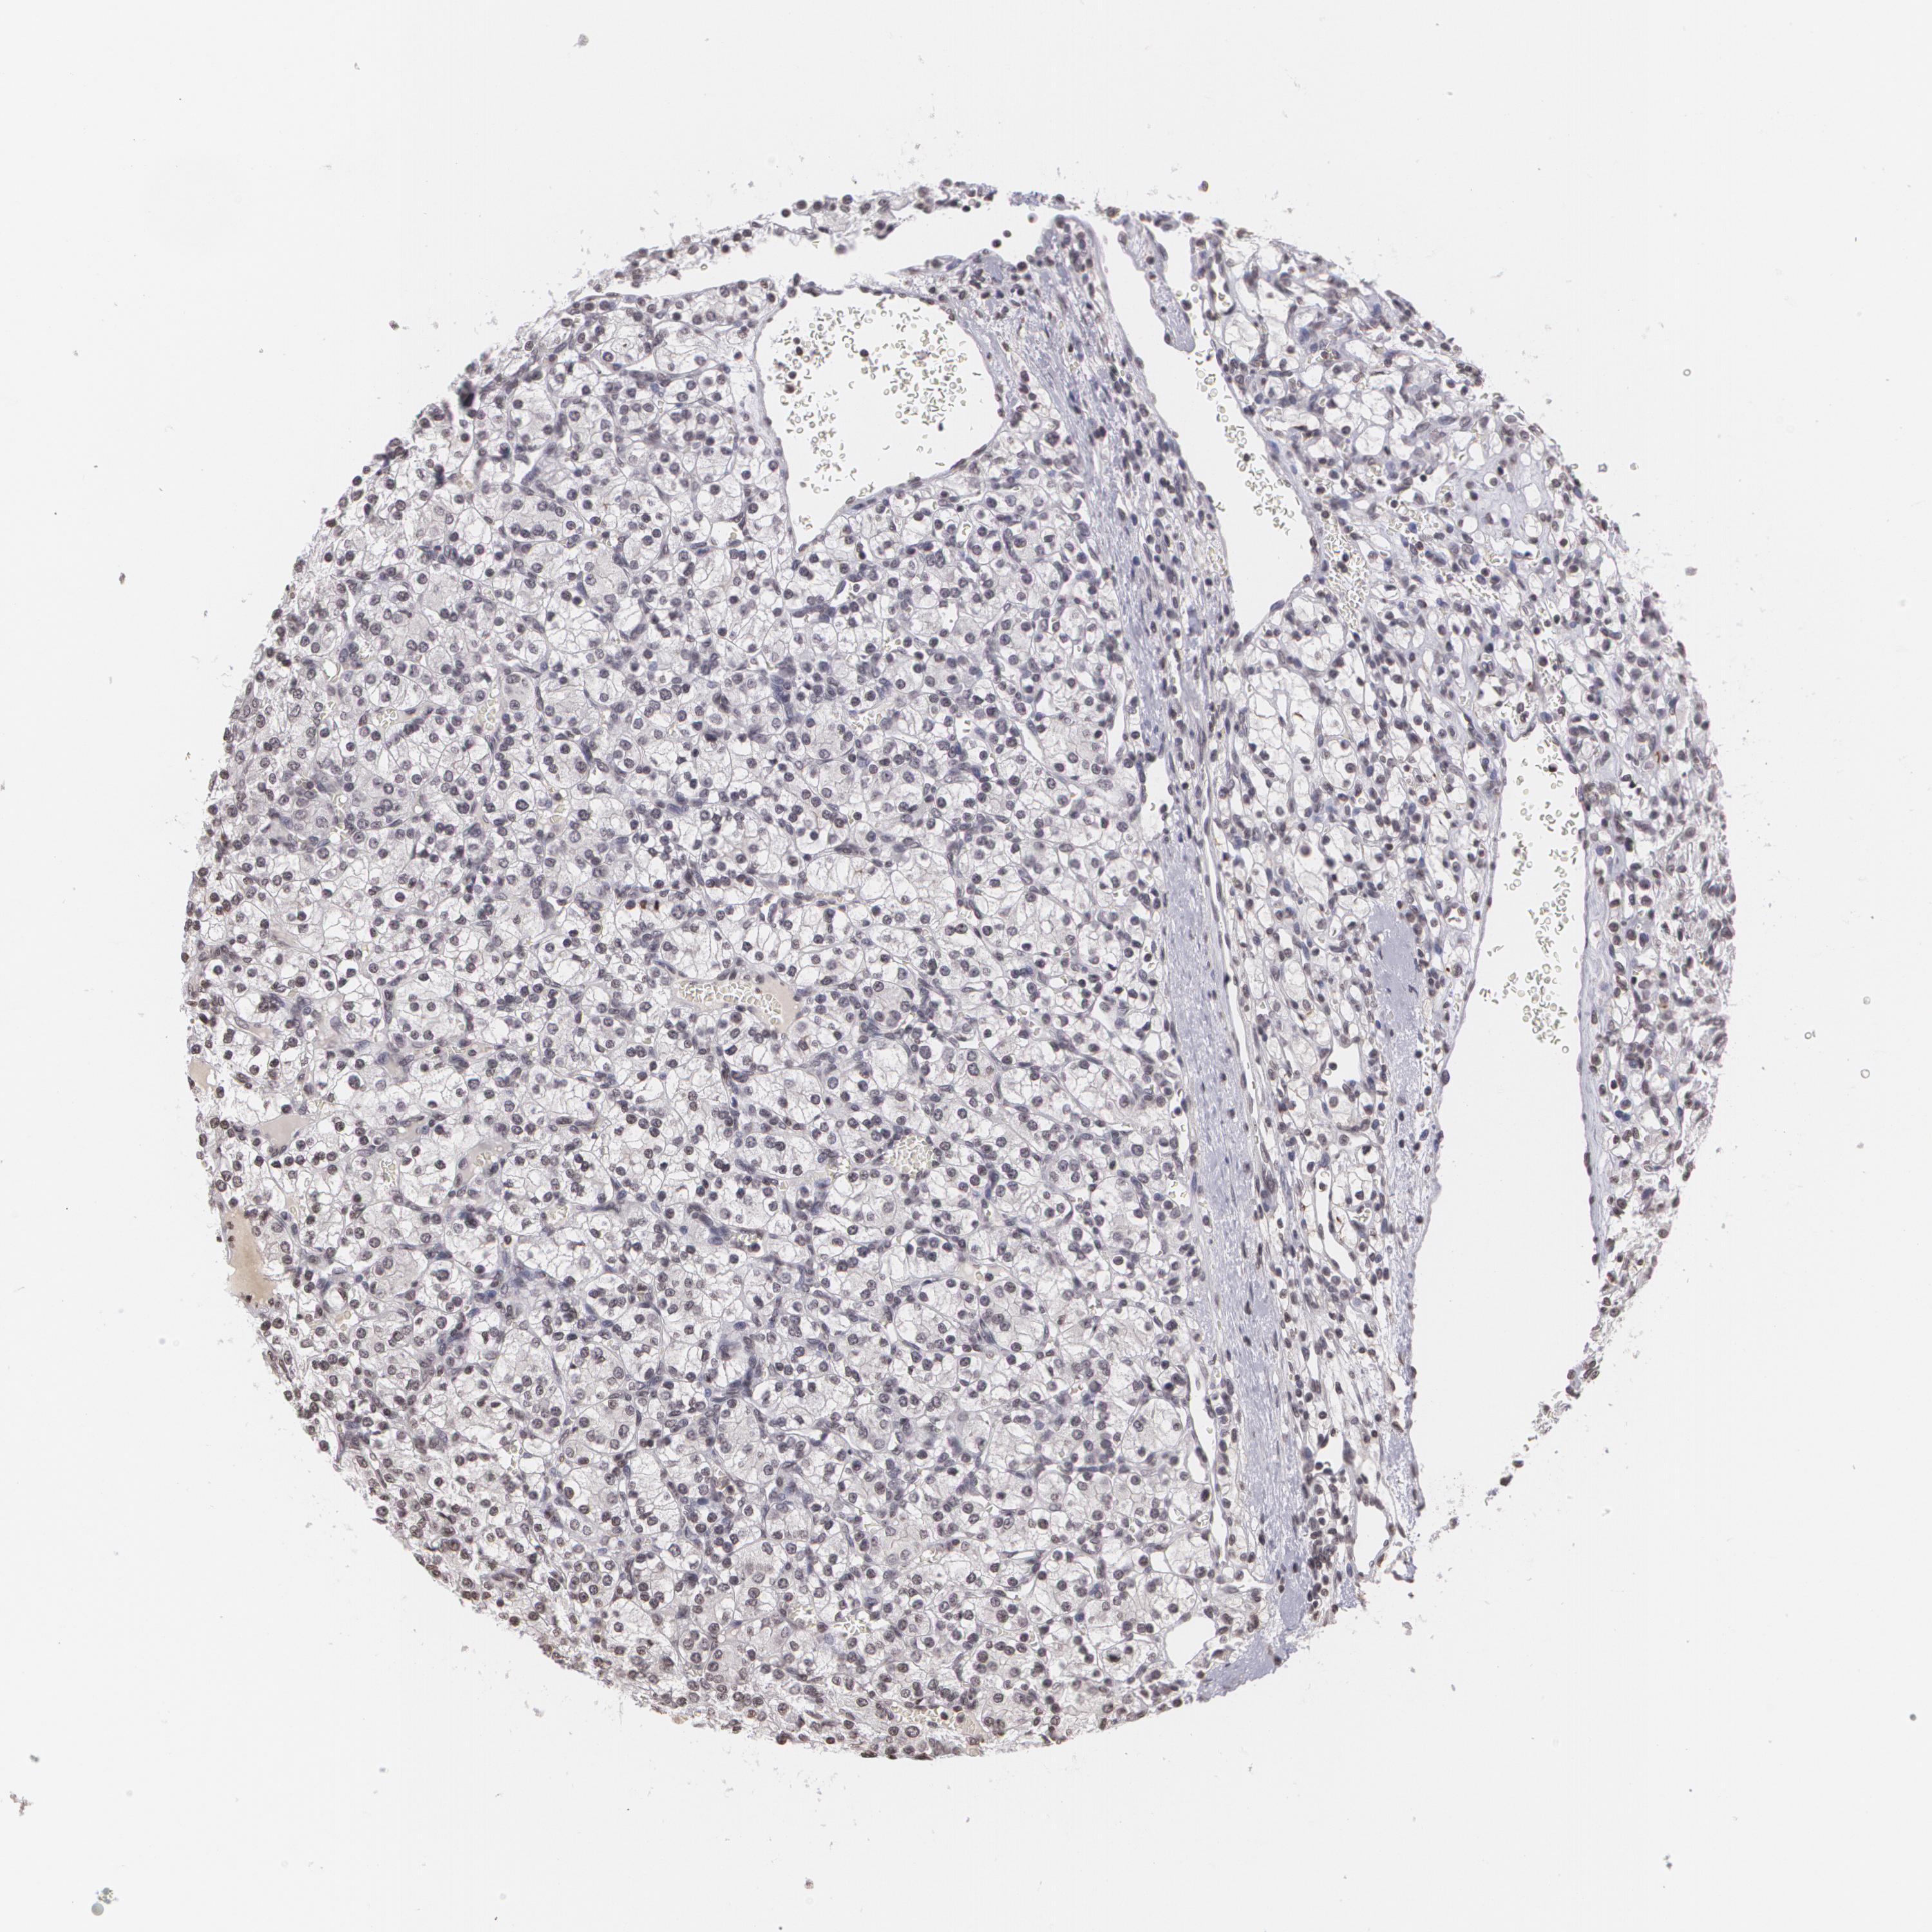

CANCER RENAL CANCER Show tissue menu

KICH TCGA KIRC TCGA KIRC VALIDATION KIRP TCGA PROTEIN RCC CPTAC PROTEIN EXPRESSION

KIDNEY CHROMOPHOBE (TCGA) - Interactive survival scatter ploti

MUC1 is potential prognostic, high expression is favorable in Kidney Chromophobe (TCGA)